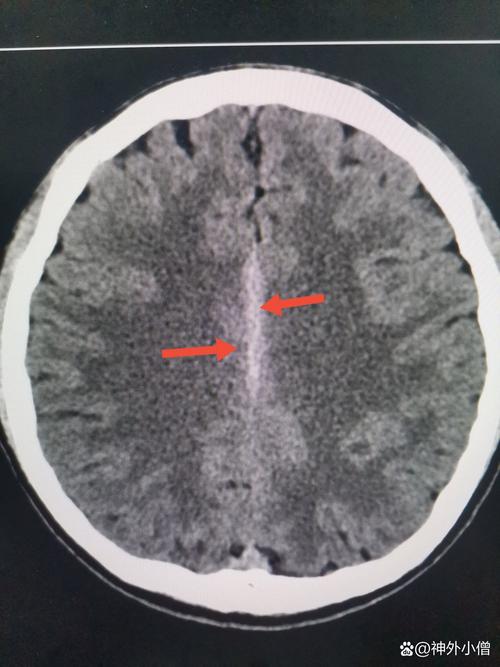

理解“毛细血管脑梗”是什么?

这个诊断描述的是梗塞灶的大小和位置。

“脑梗”:全称是“脑梗死”,就是我们常说的“中风”的一种,它指的是大脑的某一部分因为血液供应被中断,导致脑组织缺血、缺氧,最终坏死,就像一块田地因为缺水而庄稼枯死一样。

“毛细血管”:这是关键点,它告诉我们,这次堵塞发生的血管非常细小。

(图片来源网络,侵删)- 大脑的血管像一棵大树:大动脉(树干) -> 小动脉(树枝) -> 毛细血管(树叶)。

- 毛细血管是大脑最微小、最末端的血管,负责给神经细胞输送氧气和营养。

- 堵塞发生在毛细血管,意味着梗塞灶非常小,通常只有几毫米,甚至更小。

“毛细血管脑梗”的专业术语更常被称为:

- 腔隙性脑梗死

- 小血管病性脑梗死

这种梗塞因为病灶小,通常被称为“静息性脑梗”或“无症状性脑梗”,因为它很多时候不引起明显的、严重的症状,或者症状非常轻微、短暂,容易被忽略。